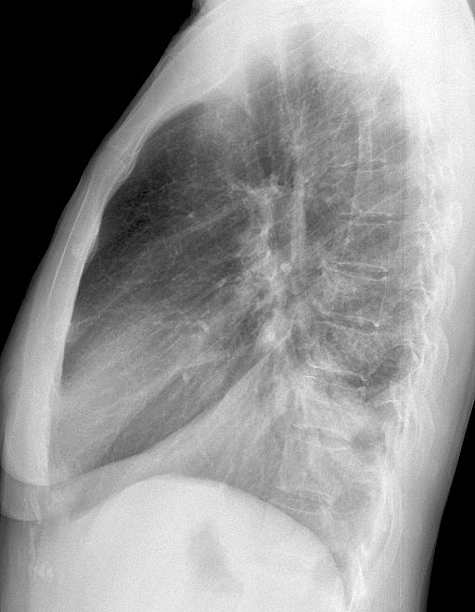

Case 8 RLL pneum Lat